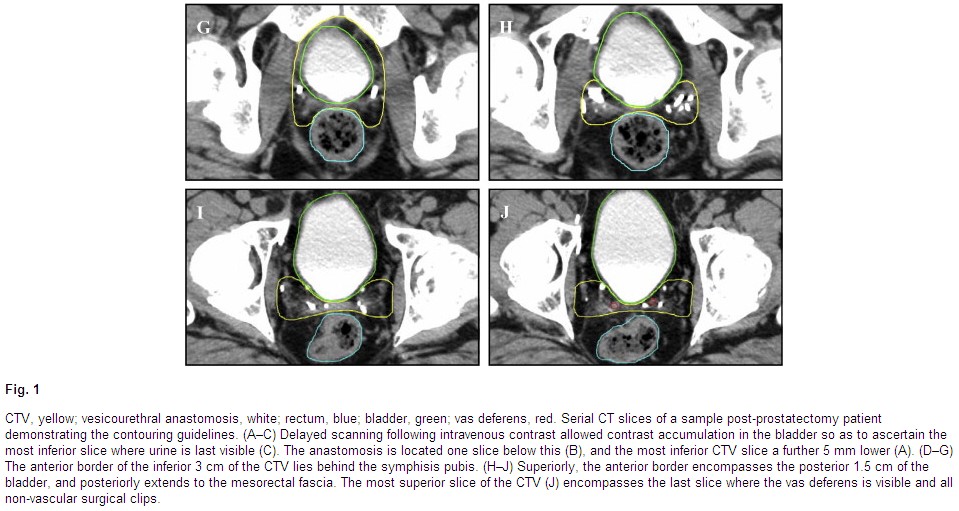

NCCN guidelines. A Typical technique from RTOG P-0011 which compares postOP radiation

alone (63 - 66Gy) with radiation plus two years of Lupron, the radiation ports are

shown here and here and here. The RTOG has

a contouring site

here, other images for contouring: